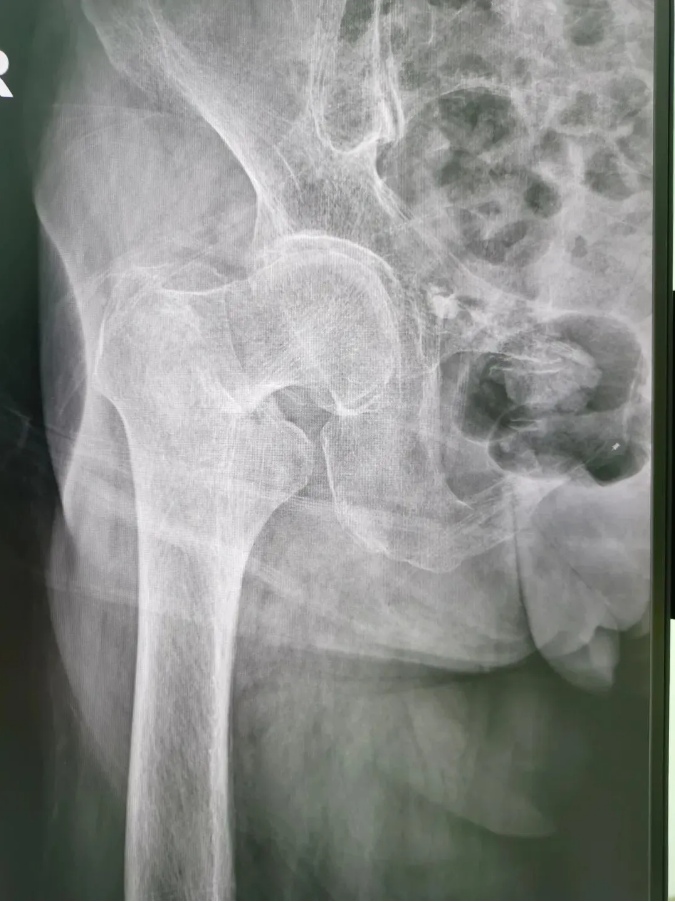

½ñÄê91ËêµÄ³ÂÆÅÆÅ£¬9Ô·ÝʱÔÚ¼ÒʧÉ÷ˤµ¹£¬ÓÒÍβ¿×ŵأ¬µ±Ï¸ÐÓ¦÷Ų¿Ç¿ÁÒÌÛÍ´²¢Ô˶¯ÊÜÏÞ¡£ÎªÇó½øÒ»²½ÖÎÁÆ£¬µ½Ë³µÂÇå¾²Íâ¿ÆÒ½Ôº¹ÇÈýÇø¾ÍÕ¸ÃÇøÖ÷ÈÎÑîÉýƽÖ÷ÈÎΪÆäÕïÁÆ£¬±»Õï¶ÏΪ¡°ÓҹɹǾ±¹ÇÕÛ¡±£¬Ðè¾ÙÐÐÓҹɹǾ±¹ÇÕ۾Ƥ±ÕºÏ¸´Î»¿ÕÐÄÂݶ¤ÄÚÀο¿ÊÖÊõ¡£

ÊõǰX¹â